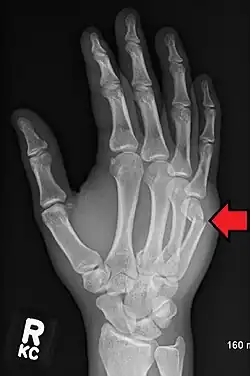

| Boxer's fracture of the 5th metacarpal head from punching a wall | |

A boxer's fracture is the break of the fifth metacarpal bone of the hand near the knuckle.[4] Occasionally, it is used to refer to fractures of the fourth metacarpal as well.[1] Symptoms include pain and a depressed knuckle.[2]

Classically, it occurs after a person hits an object with a closed fist.[3] The knuckle is then bent towards the palm of the hand.[3] Diagnosis is generally suspected based on symptoms and confirmed with X-rays.[3]

Diagnosis by a doctor's examination is the most common, often confirmed by x-rays. X-ray is used to display the fracture and the angulations of the fracture. A CT scan may be done in very rare cases to provide a more detailed picture.